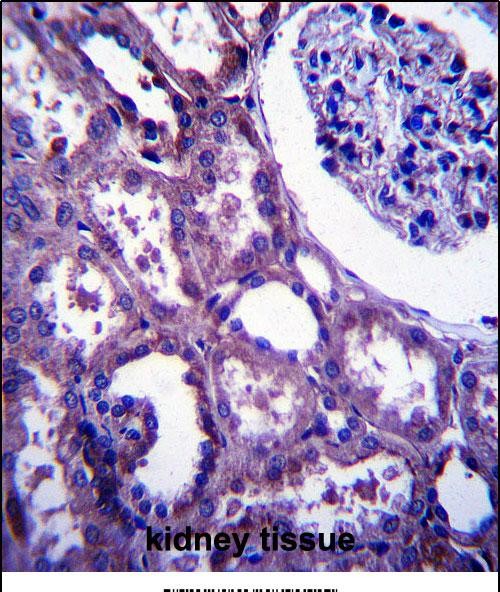

| IHC | 1/100-1/500 | Human,Mouse,Rat |

EMP2 antibodies are valuable tools for studying its expression patterns, functional roles, and therapeutic potential. They enable detection of EMP2 in immunohistochemistry, flow cytometry, and Western blotting, aiding in biomarker discovery. Recent studies explore EMP2-targeted therapies, including monoclonal antibodies and antibody-drug conjugates, to disrupt cancer signaling or enhance immune recognition. However, its pleiotropic effects necessitate context-specific evaluation in therapeutic development.